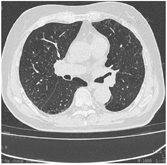

随访过程中连续2个月监测各类指标,数据显示其免疫功能、感染、肝酶、血色素、甲状腺功能等指标趋势全部好转(表1)。复查胸部CT未见肿瘤复发(图3)。淋巴细胞亚群连续免疫监控NK细胞动态趋势变化回归免疫平衡(图4、图5)。